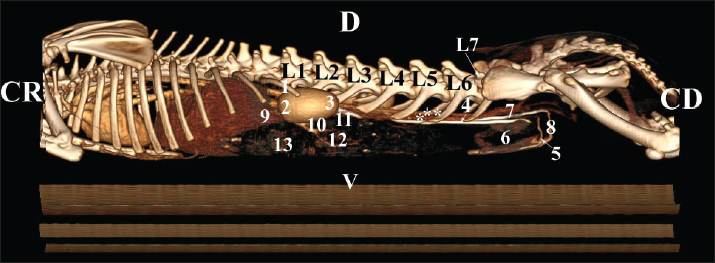

Fig. 21. Retrospective reconstruction of computed tomography data in Bones and Skin 3 mode in a rabbit. (1) XIII h rib; (2) extremitas cranialis; (3) extremitas caudalis; (4) capsula adiposa; (5) pelvis renalis (right kidney); (6) right ureter (pars abdominalis); (7) pars descendens of the duodenum; (8) pelvis renalis (left kidney); (9) left ureter (pars abdominalis); (10) lobus caudatus (proc. caudatus); (11) pars ascendens of the duodenum. Retrospective reconstruction in the Angio–Right and Left mode (right and left sides) yielded information about the localization of both kidneys in the RA. The right kidney was located in the region abdominis cranialis and region abdominis media, between Th13 (L1) and L2–L3, whereas the left kidney was located between L2 (L3) and L4 (L5) (Figs. 22 and 23).

Fig. 22. Retrospective reconstruction of computed tomography (CT) data in Angio–Right and Left 1 mode in a rabbit (right side). (1) 13th rib; (2) extremitas cranialis; (3) extremitas caudalis; (4) right ureter (pars abdominalis); (5) right ureter (pars pelvina); (6) colon; (7) left ureter (pars abdominalis); (8) left ureter (pars pelvina); (9) lobus caudatus (proc. caudatus); (10) pars descendens of the duodenum; (11) ileum; (12) colon ascendens; (13) cecum; (*) v. cava caudalis; (**) aorta abdominalis.

Fig. 23. Retrospective reconstruction of computed tomography data in Angio–Right and Left 1 mode in a rabbit (left side). (1) Extremitas cranialis; (2) Extremitas caudalis; (3) Left ureter (pars abdominalis); (4) Left ureter (pars pelvina); (5) Vesica urinaria; (6) Cecum; (7) Colon ascendens; (*) Aorta abdominalis. Statistical and metric analysesSoft tissue density was measured on pre-contrast CT scans to obtain objective data. The density of the right kidney was 40.28 ± 6.6 HU, and that of the left kidney was 43.36 ± 5.2 HU (Table 1). Table 1. CT values of rabbit kidneys in the HU.